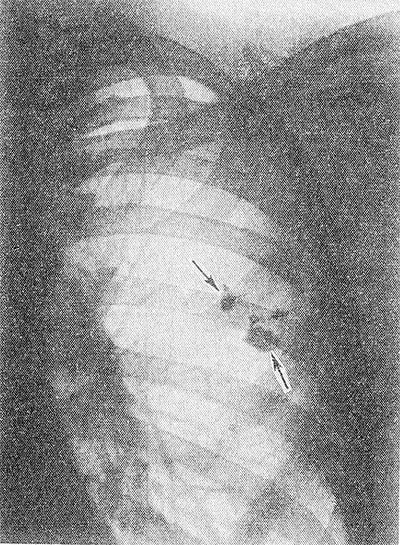

Расшифровка цифровых кодов флюорографии с примерами

01 - Кольцевидная тень (полость).

02 - Затемнение в легочной ткани (инфильтрация,ателектаз, округлая тень, среднедолевой синдром и др.).

03 - Очаговые тени в легочной ткани.

04 - Расширение тени средостения, в том числе увеличение размеров корня.

05 - Плевральные выпоты.

06 - Фиброзные изменения в легочной ткани (выраженные).

07 - Фиброзные изменения в легочной ткани (ограниченные).

08 - Повышение прозрачности легочной ткани (эмфизема локальная и распространенная).

09 - Изменения плевры (сращения, плевральные наслоения, обызвествления) выраженные.

10 - Изменения плевры (сращения, плевральные наслоения, обызвествления) ограниченные.

11 - Петрификаты крупные в легочной ткани - множественные (5 и более).

12 - Петрификаты крупные в корнях - множественные (5 и более).

13 - Петрификаты мелкие в легочной ткани - множественные (5 и более).

14 - Петрификаты мелкие в корнях - множественные (5 и более).

15 - Петрификаты крупные в легочной ткани - единичные.

16 - Петрификаты крупные в корнях - единичные.

17 - Петрификаты мелкие в легочной ткани - единичные.

18 - Петрификаты мелкие в корнях - единичные.

19 - Изменения диафрагмы, не связанные с плевральной патологией (диафрагмальная грыжа, высокое стояние диафрагмы и т. д.).

20 - Состояние после операции на легком.

21 - Изменения скелета грудной клетки (сколиоз, кифосколиоз, костная мозоль, добавочное ребро, остеофиты и т. д.).

22 - Инородное тело (проецируется на легочную ткань, тень средостения в мягких тканях).

23 - Сердечно-сосудистая патология.

24 - Прочие - добавочная доля.

25-норма.

25 - Норма.

26 - Брак.

Примечания:

При сочетании нескольких из перечисленных изменений каждое из них отмечается соответствующим кодом в каждой графоклетке.

Локализация, протяженность изменений отмечается дробью по второй графоклетке 1; 2; 3; 4; в числителе - правое легкое, в знаменателе - левое легкое (по полям).

Номер шифра легочных полей: 1 - первое, 2 - второе, 3 - третье, 4 - первое и второе, 5 - первое и третье, 6 - второе и третье, 7 - первое, второе и третье.

В третьей графоклетке вместо подписи врача подставляют личный номер рентгенолога.

Вызов на контрольное рентгеновское дообследование отмечается в четвертой графоклетке цифрой 1.